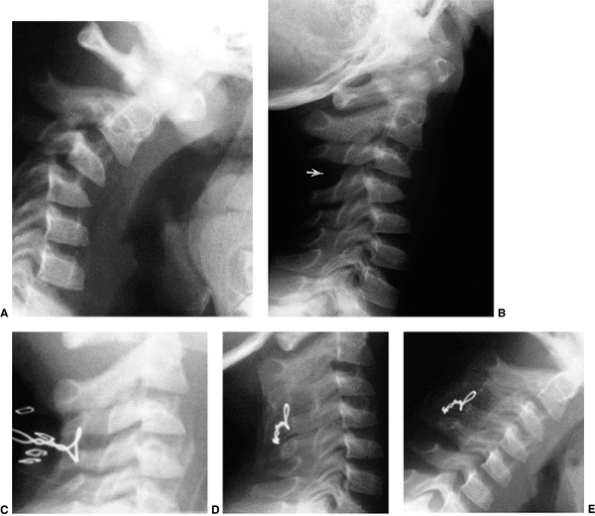

Figure 22.4 Lateral flexion (A and extension) B

radiographs of an 11-year-old boy with Down syndrome. The child presented with loss of hand control when flexing his neck. Using the method of Tredwell et al. (37), the atlantooccipital distance is measured as the distance between the anterior margin of the condyles at the base of the skull and the sharp contour of the anterior aspect of the concave joint of the atlas. More than 4 mm of posterior translation is abnormal. The atlantooccipital distance (arrows) measures 10 mm in extension and 1 mm in flexion. The atlantodens interval is 1 mm in extension and 6 mm in flexion, for a total of 5 mm of motion (arrowheads). The space available for the cord is 17 mm in flexion and 20 mm in extension. Both occipitoatlantal instability (more than 4 mm posterior translation) and atlantodens hypermobility (5 mm atlantodens interval in flexion) are present. |